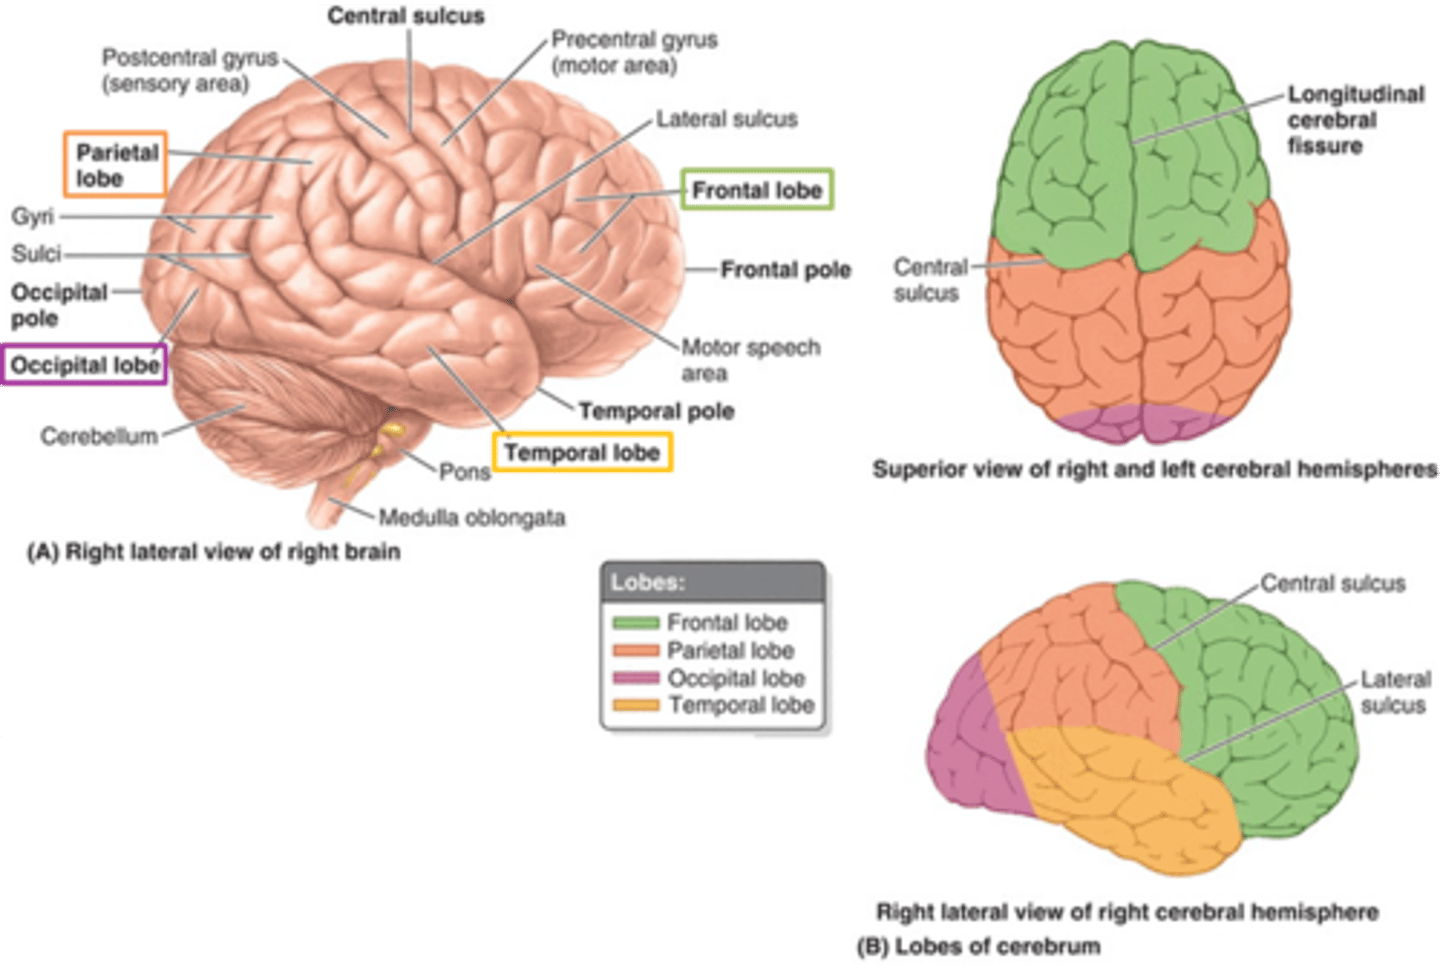

what are the 3 regions of the brain?

1. cerebrum (cerebral hemispheres)

what are the 4 main lobes of the cerebrum?

FPOT

1. frontal

2. parietal

3. temporal

4. occipital

what lobe of the cerebrum is involved with motor and personality?

FPOT

frontal

what lobe of the cerebrum is involved with sensory?

FPOT

parietal

what lobe of the cerebrum is involved in hearing and memory?

FPOT

temporal

what lobe of the cerebrum is involved in vision?

FPOT

occipital

which sulcus separates the cerebral hemispheres?

longitudinal fissure

which sulcus divides the frontal lobe from the parietal lobe and divides the precentral and postcentral gyrus?

central sulcus

which sulcus divides the parietal lobe from the temporal lobe?

lateral (sylvian) sulcus/fissure

which sulcus separates the parietal lobe from the occipital lobe?

parieto-occipital sulcus

which gyrus is the primary motor complex?

precentral gyrus

which gyrus is the primary somatosensory complex?

postcentral gyrus